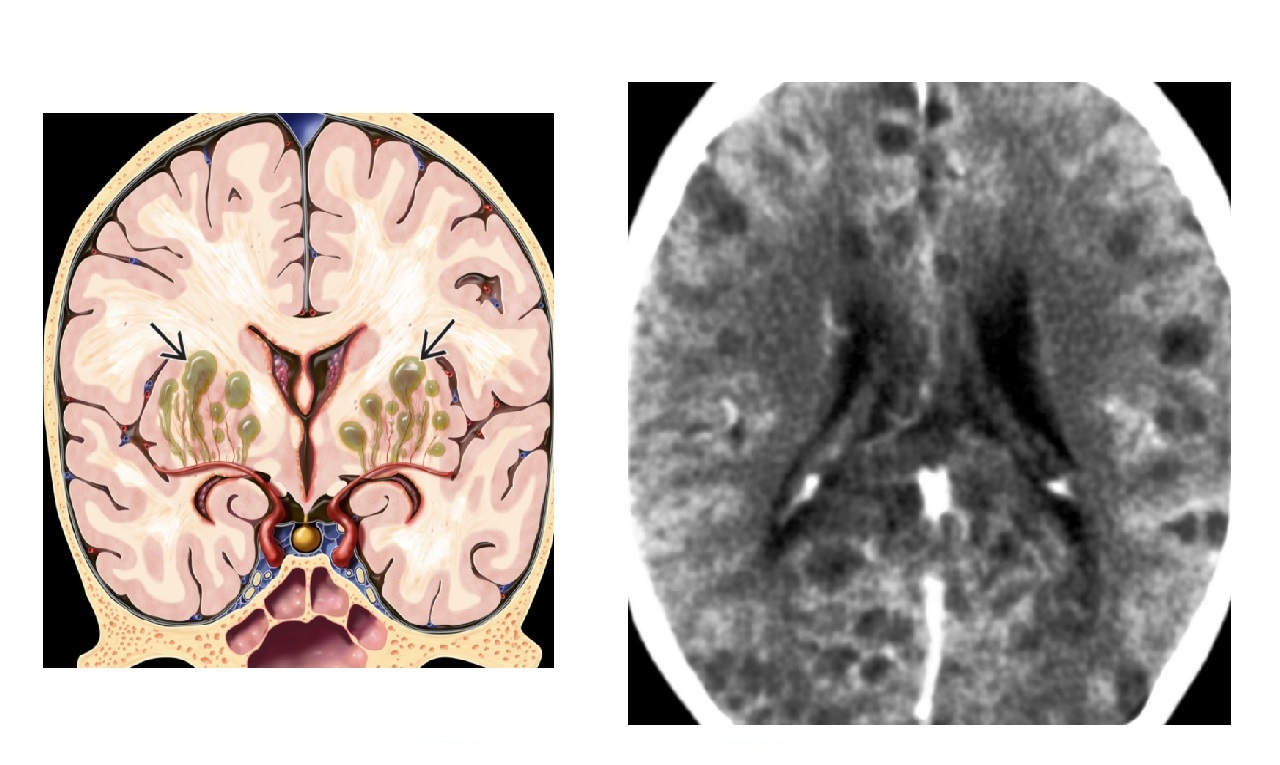

Neonatal CNS infection with basal ganglia calcifications and hydrocephalus ?

Toxoplasmosis